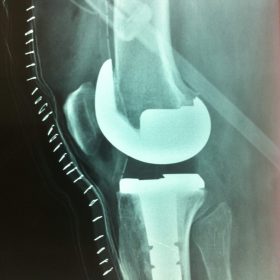

Σε αυτό το σημείο η Αρθροπλαστική Γονάτου αποτελεί μονόδρομο.